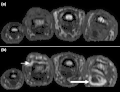

(a) STIR Sagittal MRI of ankle showing enthesitis at Achilles tendon insertion (thick arrow), synovitis of ankle joint (long thin arrow), and bone marrow edema at tendon insertion (short thin arrow). T1-weighted images, before (b) and after (c) contrast, show enthesitis (large arrow) and bone erosion at tendon insertion (short thin arrows).